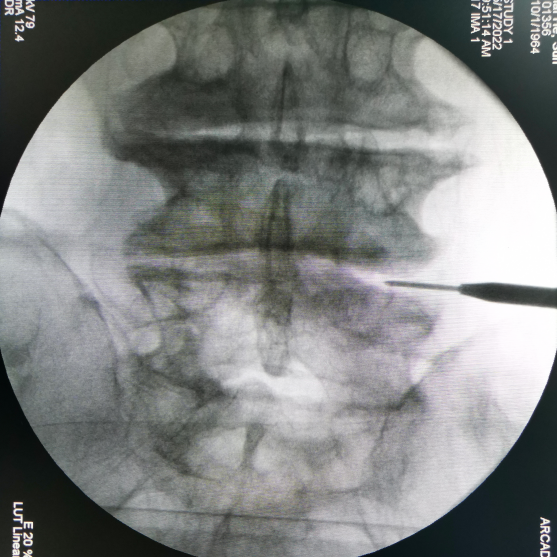

腰椎側(ce)前(qian)方椎間(jian)融(rong)合術——OLIF技術(Oblique Lumber Interbody Fusion)是(shi)目前(qian)最新的一種腰椎融(rong)合入(ru)路技術。

該術式具有創傷小、手術時間短、術中出血少、融合率高、住院時間短及快速康復等優勢,且基本不需要神經電生(sheng)(sheng)理(li)監測設備。因此,無論從臨(lin)床(chuang)效果還是從衛生(sheng)(sheng)經濟學考(kao)慮都(dou)具有相當的優勢。

安全簡單的操作方式(shi)

限深可調,融合器植入位置(zhi)更精準(zhun)